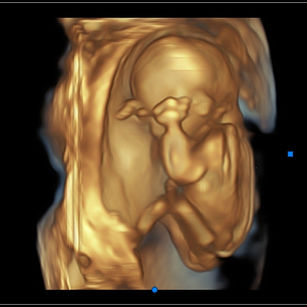

16 Weeks Pregnant

Size: ~4.5 inches (11.5 cm), the size of an Avocado!

16 Weeks 2 Days Pregnant